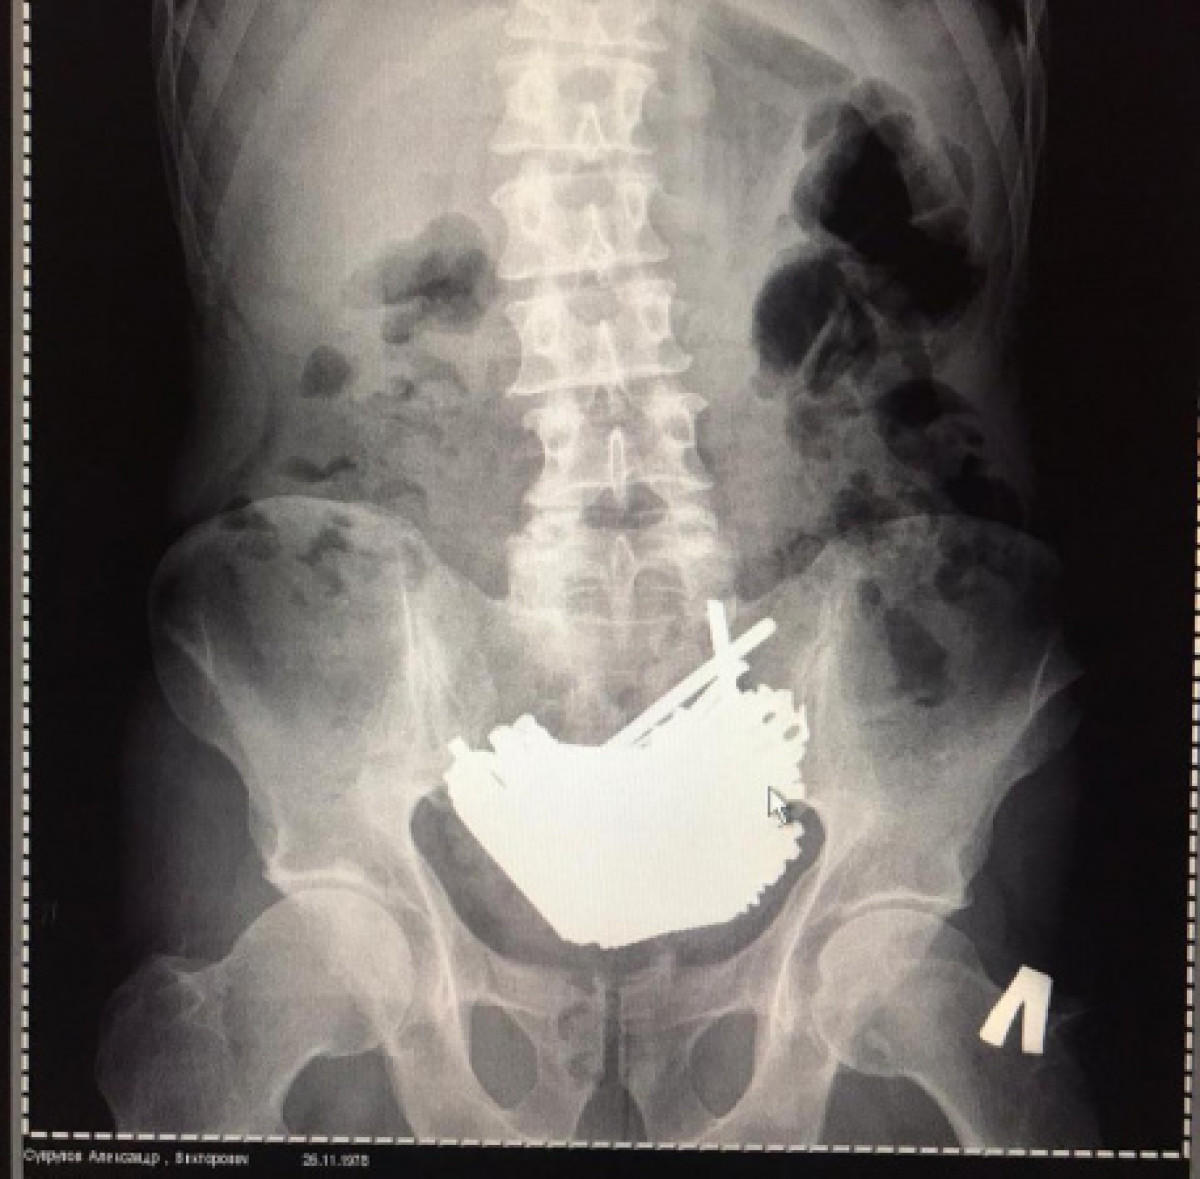

"Обследовали, провели рентген, компьютерную томографию брюшной полости. В ноябре 2019 года, со слов пациента, он проглотил металлические предметы – шурупы. Около 90 штук. В начале декабре – еще примерно 30. Срочно провели операцию", - дополнил доктор.

"Операция длилась около часа. Мы извлекли разрезанные пополам саморезы, мелкие гвозди и даже щипцы для снятия ногтей. Общий вес – 875 грамм. Что-то было в кишечнике, основная масса – в желудке. Почему они там застряли, ведь часть предметов могла пройти далее по кишечнику и выйти естественным путем? Дело в том, что "поверх всего" пациент, как выяснилось, проглотил магнит. Он и держал все комком вместе. Магнит мы тоже извлекли", - пояснил Ахметов.